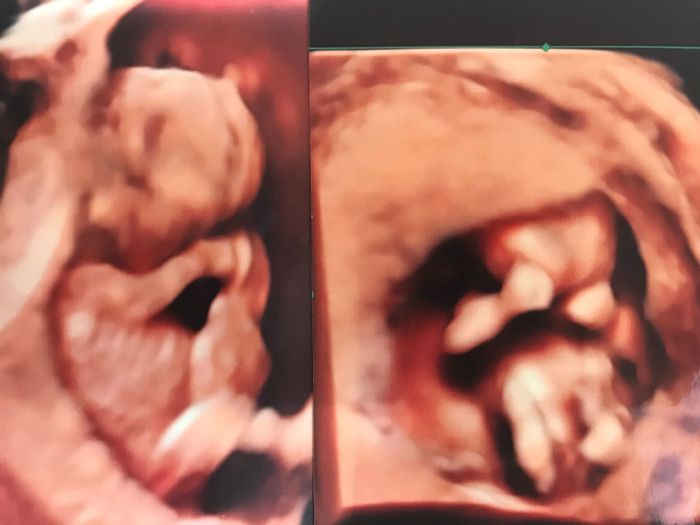

最後にしようと決めた6回目の妊娠。初期に大量出血で絶対安静の指示。副作用で思うように動けず、不安に押しつぶされそうになりながらも、毎日2本、合計約500本の注射と投薬を続けて、ようやく臨月を迎えました。